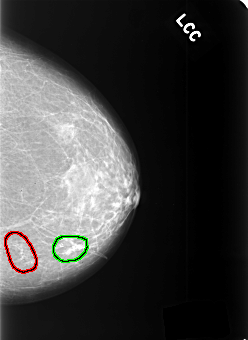

FILE: C_0361_1.LEFT_CC.OVERLAY

TOTAL_ABNORMALITIES 2

ABNORMALITY 1

LESION_TYPE CALCIFICATION TYPE PLEOMORPHIC DISTRIBUTION CLUSTERED

ASSESSMENT 4

SUBTLETY 2

PATHOLOGY MALIGNANT

TOTAL_OUTLINES 1

BOUNDARY

ABNORMALITY 2

LESION_TYPE CALCIFICATION TYPE EGGSHELL DISTRIBUTION SEGMENTAL

ASSESSMENT 2

SUBTLETY 5

PATHOLOGY BENIGN_WITHOUT_CALLBACK